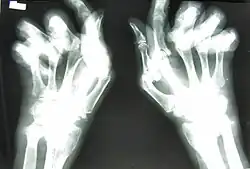

Arthritis mutilans is a rare medical condition involving severe inflammation damaging the joints of the hands and feet, and resulting in deformation and problems with moving the affected areas; it can also affect the spine.[1] As an uncommon arthropathy, arthritis mutilans was originally described as affecting the hands, feet, fingers, and/or toes, but can refer in general to severe derangement of any joint damaged by arthropathy.[2] First described in modern medical literature by Marie and Leri in 1913, in the hands, arthritis mutilans is also known as opera glass hand (la main en lorgnette in French), or chronic absorptive arthritis.[3][4] Sometimes there is foot involvement in which toes shorten and on which painful calluses develop in a condition known as opera glass foot, or pied en lorgnette.[5][6]

For a person with arthritis mutilans in the hands, the fingers become shortened by arthritis, and the shortening may become severe enough that the hand looks paw-like, with the first deformity occurring at the interphalangeal and metacarpophalangeal joints. The excess skin from the shortening of the phalanx bones becomes folded transversely, as if retracted into one another like opera glasses, hence the description la main en lorgnette. As the condition worsens, luxation, phalangeal and metacarpal bone absorption, and skeletal architecture loss in the fingers occurs.[5]

Enthesitis can assist in differentiating arthritis mutilans' parent condition psoriatic arthritis from rheumatoid arthritis and osteoarthritis, with evidence in plain radiographs (x-rays) and MRI as periostitis, new bone formation, and bone erosions.[7] Dactylitis, spondylitis and sacroiliitis are common with the parent condition psoriatic arthritis, but are not in rheumatoid arthritis.[9] MRI bone edema scores are high in arthritis mutilans and correlate with radiographic measures of joint damage, although they may not correlate with disease activity.[10] A source of significant pain, bone marrow edema (or lesions, using newer terminology), can be detected on MRI or with ultrasonography by signals of excessive water in bone marrow.[11] Specifically, bone marrow edema can be detected within bone on T1-weighted images as poorly defined areas of low signal, with a high signal on T2-weighted fat-suppressed images.[12] Comparatively, with arthritis mutilans in rheumatoid arthritis, bone marrow edema often involves the subchondral bone layer, while the condition as a subtype of psoriatic arthritis includes a greater extent of marrow edema, expanding to diaphysis.[10][13]